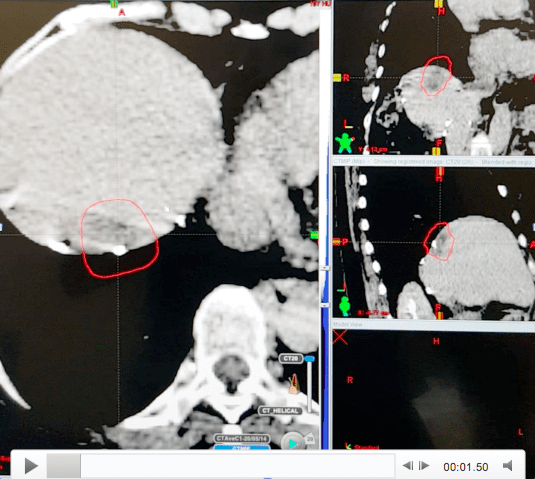

Stereotactic Body Radiation Therapy (SBRT) refers to an advanced form of external beam radiotherapy. A specialised co-ordinate system allows multiple, sharply focussed x-ray beams to hit small targets in the body. This not only allows liver tumors to be treated with great precision (therefore minimizing collateral damage), but also allows the delivery of high doses of radiation to a target within the body in either one or up to five treatment sessions. With such technology, this non-invasive method of delivering radiotherapy is now recognized as one of the options for treating liver tumours. SBRT can be employed to treat both primary and secondary liver tumours, especially those deemed not suitable for surgical removal.